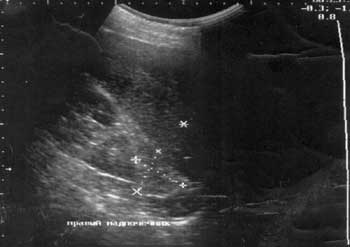

Рис. 2. Очаговая макроузловая гиперплазия надпочечника.